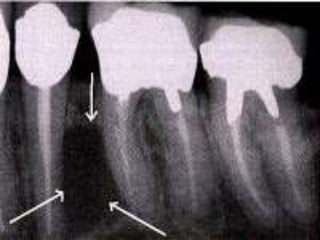

Condensing Osteitis

 4% to 8% of population

 Focal areas of radiodense sclerotic bone

 Mandible, apices of first molar

 Reactive bony sclerosis to pulp inflammation

 Irregular, radiopaque

 Stable, no treatment required

Condensing Osteitis  4%to 8% of population  Focal areas of radiodense sclerotic bone  Mandible, apices of first molar  Reactive bony sclerosis to pulp inflammation  Irregular, radiopaque  Stable, no treatment required